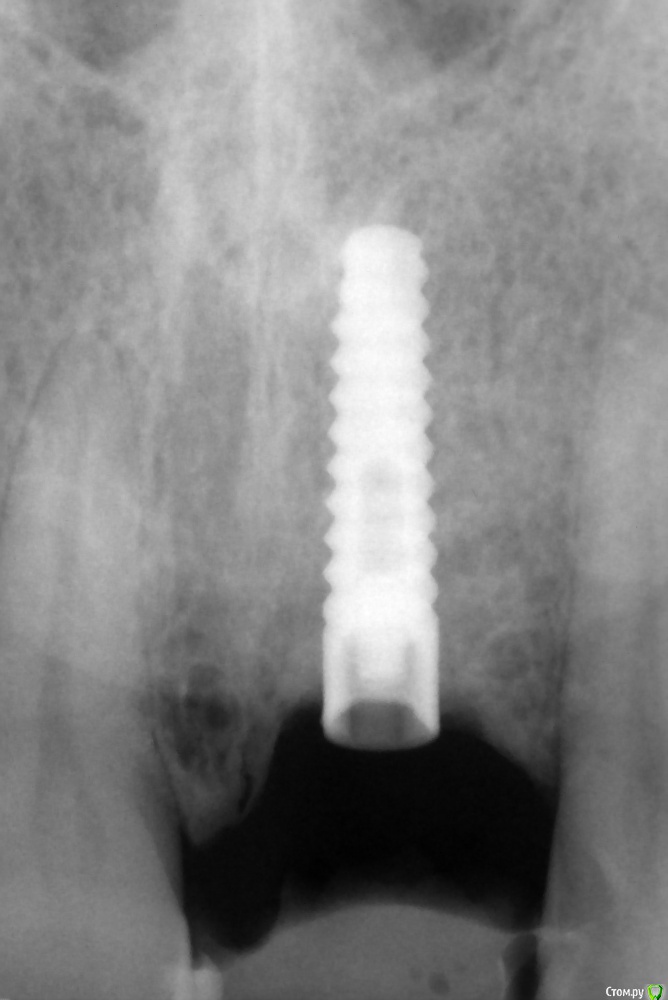

Что за имплантат?

Здравствуйте, коллеги!

Подскажите, пожалуйста, может кто признает.